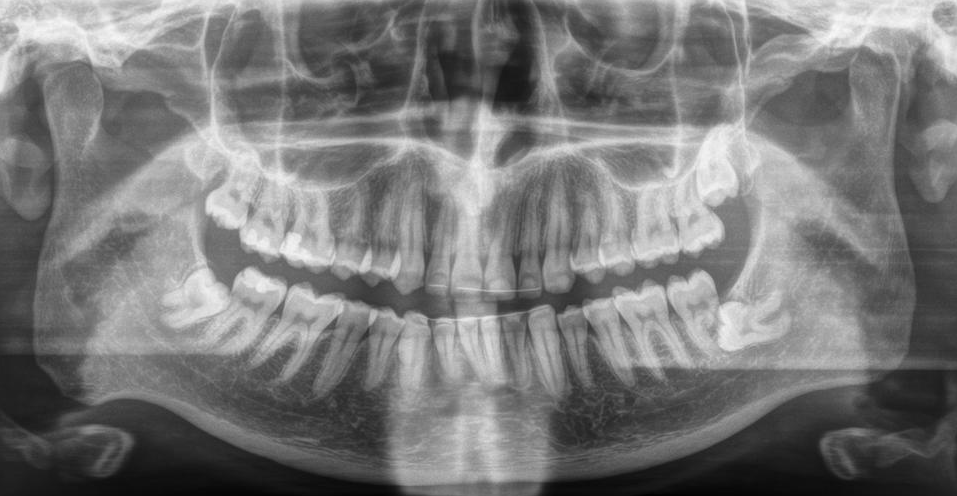

First person X-ray image displaying my teeth with a wisdom tooth visible in each quadrant, the top left one is already completely out, the others are not and the bottom right one is vertical towards and already a bit below the neighbouring tooth and has seemingly already destroyed half of its root

Left and right will be used as in first person view, therefore I mirrored this image, you’re basically looking at it from inside the head.

Also, I swear my front teeth rows don’t look that asymmetrical in reality, only a tiny unnoticeable bit if at all, maybe the X-ray’s panorama function just sux.

There was also another big question in my head: Is it even necessary to remove them? I understand that the lower right one has to be removed, it already looks like it’s been destroying part of the neighbouring tooth. But what about the others? The upper left one has come to the surface of its earth almost 2 years ago and it’s never caused me any harm, except for psychological malfunction and blurred vision. I mean except for lots of pain when it came out. Whats not wisible on the X-ray though is that it’s grown out not entirely straight, it’s facing a bit toward the inside of the cheek. But I don’t have an issue with it. Do they actually have to all be removed or is the dentist just saying so because we live in a society and the dental industry wants to profit off of me? And who thought of teeth in the back of the jaw that don’t fit and that grow in random directions and therefore have to be surgically removed?

I put my earbuds in and kept my phone in my hands to hold something and to be able to adjust the volume so I could hear them if necessary and they put a cloth thing with a hole to reach through to my mouth over my upper body (apparently also, known as surgical drape, sometimes). This also meant that I couldn’t really see anything, only a tiny bit if I looked down to the hole over my mouth. But I think I closed my eyes. I don’t remember. Anyway, the surgeon put the first torture instrument in and told me it would get a little loud now. And so it did. It was some sort of tungsten carbide drill they use in coal mining. I had read that they have to drill through the jaw bone and remove parts of it to get to the teeth if they’re still in there. Also not the nicest thing to imagine, I daresay. They started with the upper one, it doesn’t look like it’s still inside the bone on the X-ray, but it’s hard to see where the bone starts in the top row. Maybe they still had to remove parts of the bone to be able to pull it out, maybe they drilled through the side, maybe they only drilled the tooth itself apart. Either way, it was extremely loud. I couldn’t understand anything coming from my earbuds at maximum volume (and when I could hear it, I still didn’t understand anything because I couldn’t focus on it, but it was still very helpful to just hear Coldmirror’s voice). It was so loud that it hurt my ears. But fortunately no pain at all in the mouth. After only a bit, they stopped drilling and eventually started pulling on the tooth with so much force that I was literally sliding across the table or rather chair. But it didn’t feel too uncomfortable and there was still no pain, I found it rather wisible. And then it was out. And they went on with the bottom one. And it got loud again. Even louder than last time. It actually hurt my ears so much that I really wished it would stop, verrry soon. Imagine standing next to a fire truck with an active siren. Maybe it was louder because they actually drilled through the bone itself this time, it definitely looks like they have to on the X-ray. Maybe for some other acoustic reason. When they finally stopped, it didn’t take too long either, I was told I would hear a crack soon. Something cracked with a rather disgusting noise, but I didn’t have much of an issue with it. I assume they snapped the tooth in half to get it out. And not long after, a little gauze roll was put between my back right teeth, I was told to firmly bite on it for half an hour and it was over. According to how much of the podcast had elapsed, I later found out that ze procedure itself took exactly ten minutes. My mum told me later that her wisdom teeth surgery, she only had three fortunately, took very long, like at least twenty minutes for one tooth and they kept saying they’ve almost got it, they could already see it. Maybe medicinal procedures have improved over the last 30 years. Maybe she was just unlucky. Maybe her surgeon was bad. Maybe I was lucky and my surgeon good. Maybe a combination of those. Who knows. Either way, I was very relieved it was over already and I hadn’t felt any pain. At least in my mouth. I was told to take the first painkiller dose when I’m at home, that I should make a followup appointment at my dentist so I don’t have to get all the way here just for checkup and stitch removal and that I would get some papers at the reception. So I went to the reception and was given an information sheet printed on both sides, two prescriptions for painkillers and mouth wash and the sick note. Then I was free to go.

The operation itself was definitely the part I feared the most, which was fortunately over now. The part I feared the second most was the stitch removal. Pulling threads through my skin out of wounds sounds disgusting and painful. And it sounds very primitive. Surely there must be better ways to close wounds nowadays. I asked myself the same when I was at the orthodontist recently to get my upper front inner retainer replaced (you can see the old one in its broken status in the X-ray) and they made a dental cast of my upper jaw, just like back then for my braces. How positively medieval. We can make detailed 3D scans of people to use as digital models but we still use these stone-age methods in the medical field. And glueing a 2 cm wire to teeth apparently costs as much as a medium-end smartphone. That will most likely break over and over again, making the braces I had useless because it’s impossible to hold the teeth in place without them. Back on the topic of needle and stitch in my pants. As usual, I was especially nervous about this part because of that one or rather two times when I was a child and I was circumcised which were horrible and painful weeks, the most pysically painful time in my life, and removing those stitches was very painful as well.

I got an appointment for the other side: 2021-10-22, exactly 8 weeks after the first one. I better get to the Halloween fideo quickly. I also just ventured around with my tongue a little more. I don’t feel any irregularities anymore, only that the upper gum goes up a bit after the last tooth, which makes it feel a little like an upside down valley between the tooth and the back of the mouth, where the wisdom tooth used to reside. It’s not like this on the upper left side, obviously, since that’s where the wisdom tooth is completely out. I don’t remember exactly how it was and felt before, though it must have been at the same level as the second molar area since that wisdom tooth was about to get out as well and the gum was touching the lower gum for a bit while the tooth was moving. But I think it’s been similar to this “valley” before that wisdom tooth moved further down, like when it was still in the state of the X-ray above.

Then I explained the situation with my bottom right first molar. I don’t think I’ve done that here yet. A couple of months ago, I got a filling in that tooth at my local dentist. A month later, I started feeling pain sometimes when biting on that tooth in a specific spot. The typical disgusting tooth pain. Not as bad as it could be, but not the nicest feeling either, but at least it disappears immediately once I stop biting on whatever caused it, unlike that other tooth in January that took hours to stop hurting. But it definitely prevents me from eating on that side. So I went back to the dentist, the tooth was looked at, but they didn’t see anything. They took an X-ray and nothing seemed to be wrong there as well and the filling was apparently not very deep. But that one horizontal wisdom tooth was visible on that X-ray as well, so they said that that might be the cause, though I considered it unlikely since I was pretty sure it was the first molar and the wisdom teeth only impacted the second molar. They removed a bit from the top of that filling and put some stuff on it and told me to go and see if removing the wisdom tooth fixes it. Since the first surgery, I’ve only been chewing on the left side. But I’ve become less careful recently and a couple of times some food sneakily sneaked over to the right teeth. And I again and still felt that pain in the first molar. Apparently it had nothing to do with the wisdom tooth. The surgeon said that it’s possible that the filling applies pressure to sensitive or damaged parts and removing more of it could help. I think they said that, I don’t remember things well when I’m nervous. I had planned to ask some more questions regarding the utilisation of straws and so on, but after that they started to proceed with the local anaesthesia and I didn’t feel like asking more questions, I just wanted it to be over. So if you want to know the answers: Ask your surgeon yourself, I guess.

I was told to wait outside to the right on the green bench to have an X-ray taken. I put my phone and earbuds into my pants’s’s pockets, taking a while to nervously stuff the cables in there, and then took my jacket that I was very focussed on not to forget. In fact, I was so focussed on not having forgotten my jacket and the surgery that just happened that I forgot to get my facial masking device out and back on, the surgeon had to remind me as I was about to leave the room body. In the X-ray room, I was told to bite on that thing on the device as usual, but I also had that gauze in my mouth I had to bite on, so I asked about that and was told that it doesn’t matter. I was also wondering if taking an X-ray now is a good idea since I’ve already had a full teeth X-ray at the beginning of the year and two spot ones, and another full one would probably be useful once both sides are supposed to be fully healed. A physics teacher told us that like three times or something is the maximum amount of X-rays one should get per year to avoid risks and therefore one should always tell doctors of any recent ones. But I didn’t feel like or was fully able to discuss that and possibly object to their professionaly planned proceedings. I haven’t had an X-ray taken since my braces were taken off like 8 years ago (subsequently they told me that I have 4 wisdom teeth that will eventually have to be taken out and expressed their condolences (Hi, young Phalio of 8 years ago worrying about the surely painful process of having them cut out of the jaw, it’s finally over and it went well!)) and the two X-rays that only contaminated small areas of my jaw might not be as bad as bigger ones, so I hope it’s alright. I’ll put the new X-ray here if I’m able to get my hands on that one as well. Why are medical practices allowed to decide not to give X-ray images to their patients and only allow them to view them on-site? Anyway, the receptionists gave me the same information sheet as last time and only one prescription, one for the mouth wash and none for painkillers. Prescription-free paracetamol it is. Let’s hope it’ll be enough.

But the dentist didn’t say anything about that, so I guess it’s either normal or irrelevant. First I was shown the new X-ray for the first time. I was only shown the bottom right ex-tooth area, the bad one from last time, I didn’t see the whole image and not the left side that was freshly surged at the time the X-ray was taken. But that one ex-tooth still showed a big hole in the jaw bone. Interesting to see, and also a little scary. But what I immediately noticed was that the roots of the second molar that appeared to be partly gone in the X-ray from before were all there and seemed perfectly intact! So I guess they weren’t destroyed by the wisdom teeth and it somehow was before or behind them or something and the perspective of the X-ray just hid them. The dentist proceeded taking cold tests (no idea if they have a name, they hold a very cold piece of cotton or something against a teeth to test if the nerves are still reacting to it as they should be) on the first molar there that I’ve been having issues with and deemed it perfectly fine once again. Otherwise they couldn’t do anything now as they said they have to wait for the bone to fully heal before attempting stuff like remaking the filling or something, and maybe it’ll be fine by itself after it’s healed. I wonder for how much longer I’ll be having pain in that tooth. Maybe having survived the trial of wisdom won’t be the end of annoying and anxiety-inducing teeth stuff after all. But after having survived teeth being cut deep out of the jaw bones and not having felt any pain at least during the procedure might have cured my fear of dentists. After all, what’s a mere tiny or even larger filling or possibly root canal compared to that? Or even just routine Chekup or professional tooth cleaning?The dentist also said that the ex-teeth look well and that I should come back on Friday (exactly a week after Toothday) to have the stitches removed.